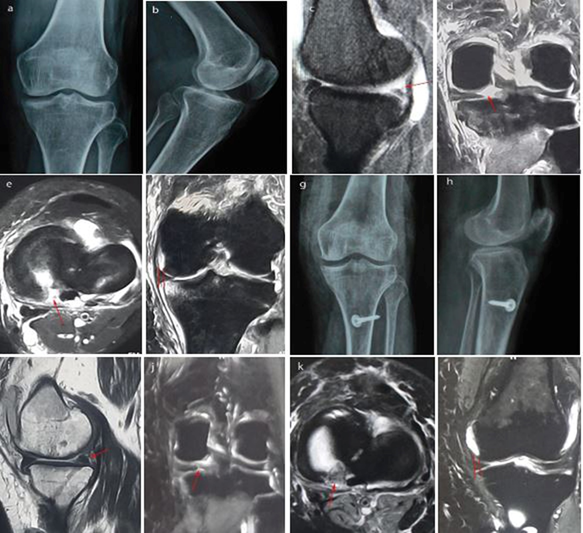

Out of 10 patients, 2 are male and 8 are female. The male: female ratio is 1:4. Mean age of the patient is 64 years (Range, 60 – 75 years). The mean follow-up period is 30 months (Range, 24-36 months). Mean BMI of the patients is 26.14 + 1.95 kg/m2 (Range, 22.5 – 29.2 kg/m2) (Table 1). No patients complain of pain, catching or giving way. No patient had joint line tenderness or effusion. The difference in mean preoperative and postoperative patient’s IKDC and Lysholm score are significant (Table 2). Follow-up MRI is performed in all the patients in which only 2 patients show complete meniscus root healing (Figure 2), 8 patients show partial meniscus root healing (Figure 3) and there was no case of repeat tear. Mean extrusion of meniscus decreases from 5.2 + 0.8 mm (Range, 4 -7 mm) preoperatively to 4.13 + 0.55 mm (Range, 3.5 - 5.2 mm) postoperatively, respectively.

Figure 2 Preoperative left knees.

a) Anteroposterior. b) Lateral radiographs. c) Preoperative MRI showing root tear (red arrow) in sagittal. d) Coronal. e) Axial. f) Meniscus extrusion (measured between two red vertical lines). g) Radiographs at 3 years follow up anteroposterior. h) Lateral view. i) MRI scans at 3 years follow up showing complete healing (red arrow) on sagittal view. j) Coronal view. k) Axial view. l) Coronal view showing decrease meniscus extrusion (measured between two red vertical lines)